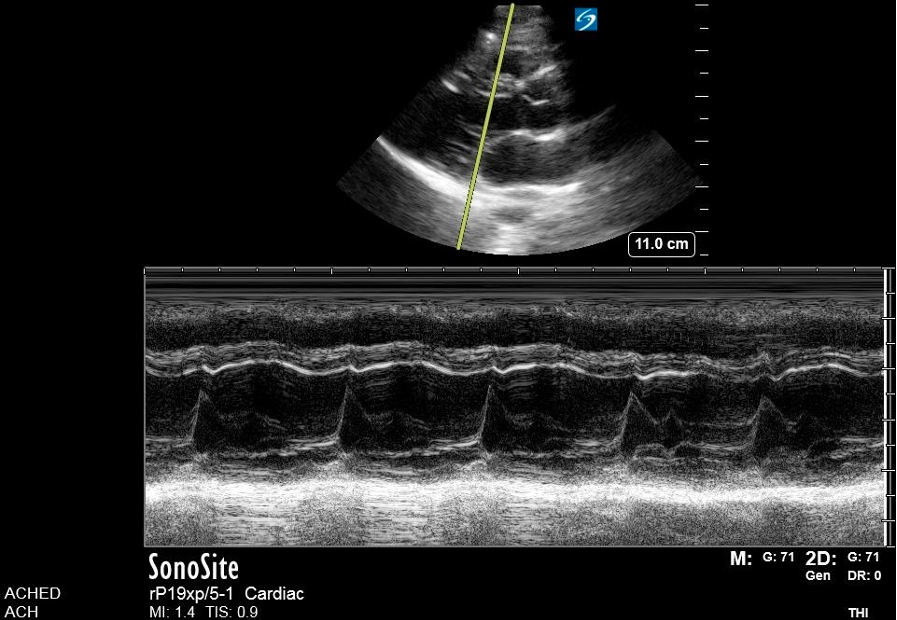

PLAX M-Mode

In the PLAX view, M-mode is commonly used to assess LVfx by placing the cursor perpendicular to the IVS and posterior wall at the level of the MV tips. This provides a time-motion trace of LV wall motion and cavity size throughout the cardiac cycle, with distance displayed on the y-axis and time on the x-axis allowing evaluation of systolic function.

You’ll see a wave-like motion tracing of the MV leaflets movement across the cardiac cycle. In early diastole, the AMVL rapidly opens toward the IVS, creating the tall E-wave, followed by a smaller A-wave from atrial contraction (figure 7,8).

Figure 7. M-mode

Figure 8. Zoomed-in view of the PLAX M-mode tracing at the level of the mitral valve tips.